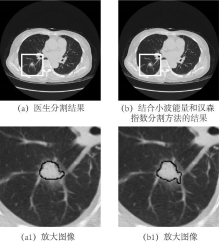

(3)基于CT影像的亚实性肺结节良恶性预测关键技术研究

国家自然科学基金项目《基于CT影像的亚实性肺结节良恶性预测关键技术研究》,与中山大学附属医院江门市中心医院开展合作,建立了医学人工智能实验室。结合临床信息,形成医学大数据,研究小样本下的深度学习特征提取算法模型、分类算法模型,构建了实性肺小结节良恶性辅助诊断模型、亚实性肺结节辅助诊断模型等,并利用多中心临床数据进行模型验证分析。目前已经联合放射科医生发表SCI、EI期刊检索论文30余篇。此外,与医院康复科合作,开展基于脑机接口技术的康复系统开发,搭建了基于单通道、多通道脑电信号的主动式上肢康复系统。

图3 亚实性肺结节实性成分分割算法及结果展示